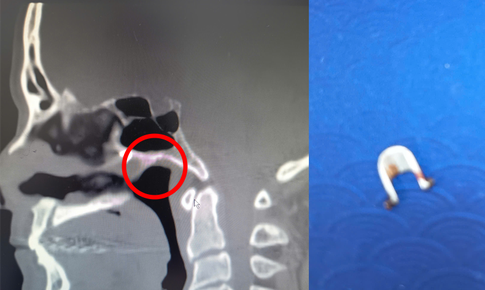

Tắm ở suối, bé trai 4 tuổi bị vắt chui vào mũi

Y tế - 03/10/2025 16:23SKĐS - Sau khi đi tắm suối về, bé 4 tuổi ở Quảng Ninh thi thoảng lại bị chảy máu mũi. Tình trạng kéo dài, khi đi khám tại Bệnh viện Việt Nam – Thụy Điển Uông Bí, cả nhà sửng sốt khi thấy một con vắt sống trong hốc mũi con.